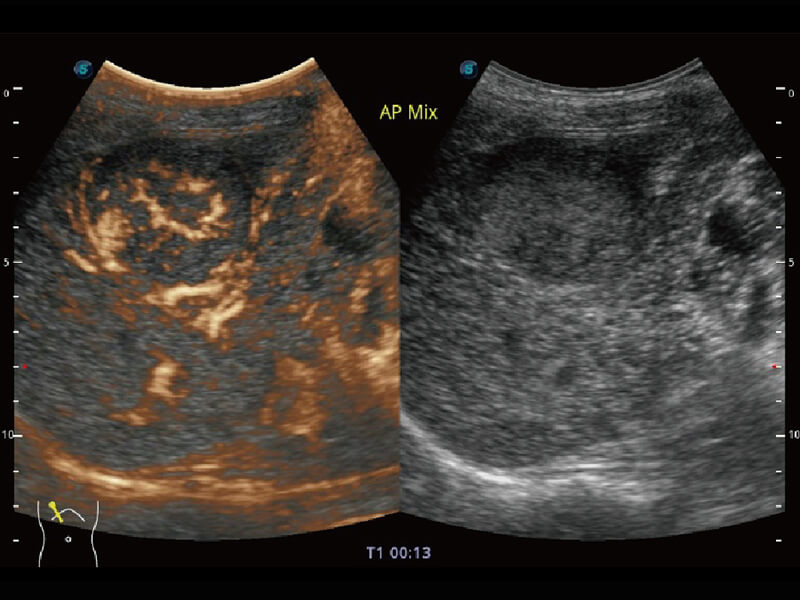

超宽频带技术,为容积成像带来优质的二维图像基础,为您呈现丰富的结构细节,栩栩如生地展示宝宝的宫内形态以及各种组织的立体结构。